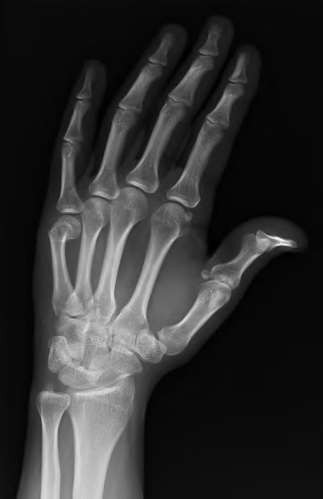

A 35-year-old woman reports wrist pain after a fall onto an outstretched hand. On exam, she has focal tenderness over the wrist snuffbox. A radiograph and CT image are shown in Figures A and B. What is the proper treatment of her injury?